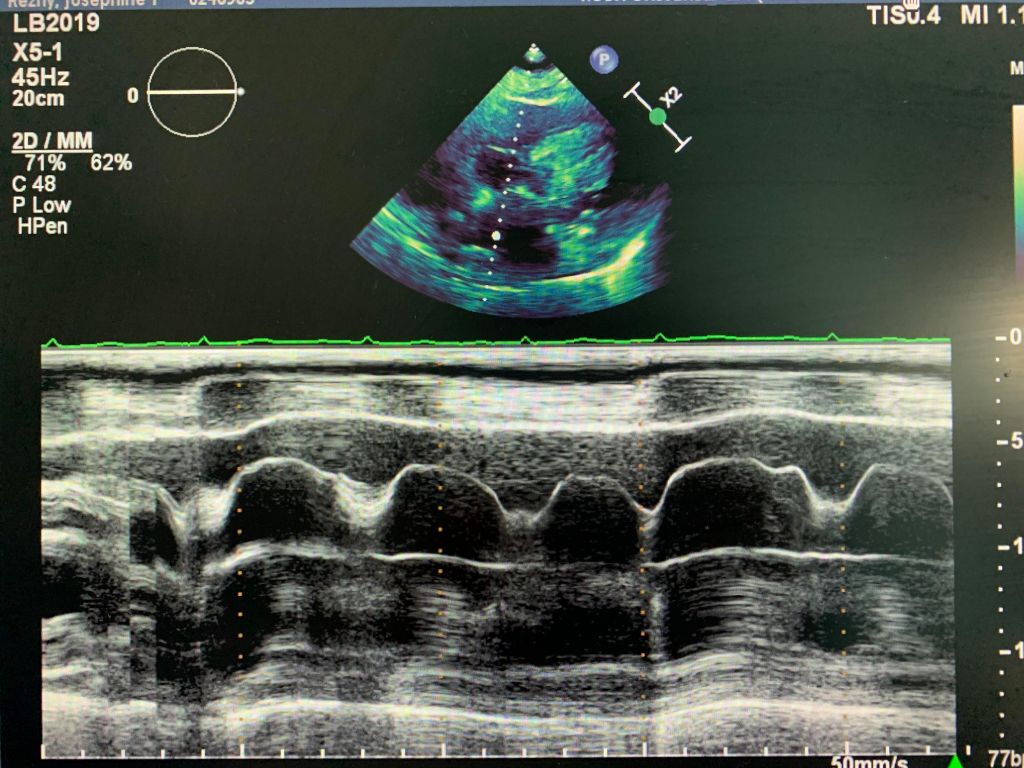

A 78 y/o Female presents for complete echocardiogram with a history of dyspnea on exertion. Patient is on 4 L of oxygen, unable to breathe laying supine. Breathing gets better as she sits up. Below are just a few images of her echo.

It was agreed by the physicians that the patient had a large pericardial effusion and her right atrium was collapsing. Further treatment to be determined.

Below pictures are taken from the SUB4 view only, as the patient’s respiratory variation didn’t show any changes.